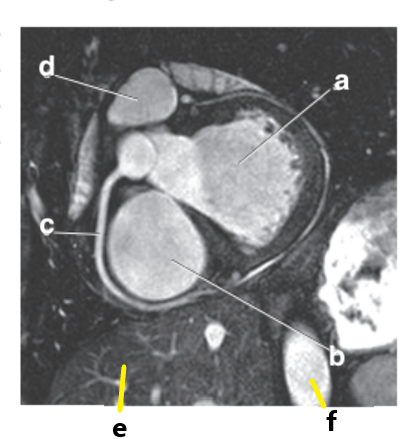

Left ventricle

What is letter a?

Which letter is the ascending aorta?

f

What is letter c?

Aortic arch

Ascending aorta

Descending aorta

Interventricular septum